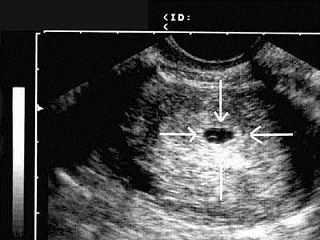

Внематочная беременность

➔Как ты знаешь, оплодотворение происходит в маточной трубе. Оплодотворенное яйцо проходит по трубе к полости матки и имплантируется в ней. Внематочная беременность имеет место, когда имплантация происходит вне пределов матки, обычно в маточной трубе. До 95 процентов внематочной беременности приходится на трубную беременность, в остальных случаях местом имплантации может стать яичник, рудиментарный рог или шейка матки. Когда плодное яйцо выходит (выпадает) из трубы в брюшную полость, происходит так называемый трубный аборт.

Внематочная беременность имеет место в одном случае из ста. Причинами внематочной беременности могут стать воспаление тазовых органов или иные инфекционные заболевания, такие как воспаление аппендикса. Если ранее у тебя уже была внематочная беременность, вероятность рецидива составляет 12 процентов. Применение внутриматочной спирали увеличивает риск внематочной беременности.

Диагностика внематочной беременности

➔Диагностика внематочной беременности сейчас основана на методе тонкой хирургии лапароскопии. Через маленький надрез в пупке и нижней части брюшной полости внутрь вводится эндоскоп, позволяющий осмотреть тазовые органы и увидеть внематочную беременность.

Выявить трубную беременность необходимо до того, как произойдет разрыв и повреждение маточной трубы, что может вызвать необходимость ее полного удаления. Ранняя диагностика внематочной беременности помогает также снизить риск внутреннего кровотечения из поврежденной маточной трубы.

При внематочной беременности тест на беременность дает положительный результат несмотря на то, что эмбрион развивается вне пределов матки, поскольку он выявляет гормоны, вырабатываемые на ранней стадии беременности хорионический гонадотропин человека (ХГ). Эти гормоны можно обнаружить в крови или моче.

Выявление внематочной беременности лабораторными методами

➔Тест на беременность дает положительный результат (женщина беременна) или отрицательный (не беременна). ХГ может быть измерен также и количественно, что важно для диагностики внематочной беременности или выкидыша. Уровень ХГ повышается очень быстро в условиях нормальной беременности удваивается примерно каждые два дня. Если количественного роста не происходит, это дает основания заподозрить осложненную беременность.

Ультразвуковое обследование (УЗИ) часто помогает выявить внематочную беременность. Трубную беременность можно буквально увидеть на УЗИ. Следует отметить, что при внематочной беременности у женщины может наблюдаться довольно высокое содержание ХГ без всяких признаков беременности внутри матки, которую легко выявить с помощью УЗИ. При внематочной беременности можно заметить кровотечение в брюшной полости или сгустки крови в районе фаллопиевой трубы или яичника.

В случае внематочной беременности цель врача удалить эмбрион, сохранив при этом фертильность (плодовитость) женщины. Обычно это очень трудная задача, поскольку выявить внематочную беременность на ранней стадии достаточно сложно. Распространенные симптомы влагалищное кровотечение, боли в брюшной полости, повышение чувствительности груди, тошнота являются также симптомами нормальной беременности. В большинстве случаев внематочную беременность удается обнаружить на 6-8-й неделе беременности, хотя иногда несколько раньше или позже. Ключ к ранней диагностике в твоих руках: постарайся описать врачу как можно подробнее все свои симптомы и степень их «тяжести». Внематочная беременность очень опасна внутренним кровотечением и возможным дальнейшим бесплодием.